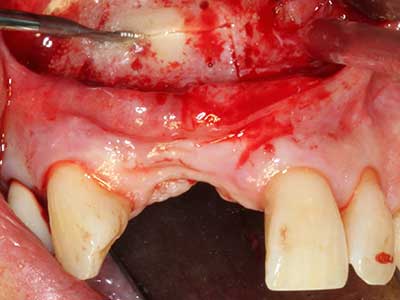

Fig. 18: preparazione di una copertura corticale con sega piezoelettrica per osso (Piezomed, W&H).

Fig. 19: sito chirurgico dopo neurolisi e rimozione dell'osteoma.

Fig. 20: la copertura ossea rimossa viene riadattata e fissata con una vite per osteosintesi (KLS Martin, Tuttlingen).